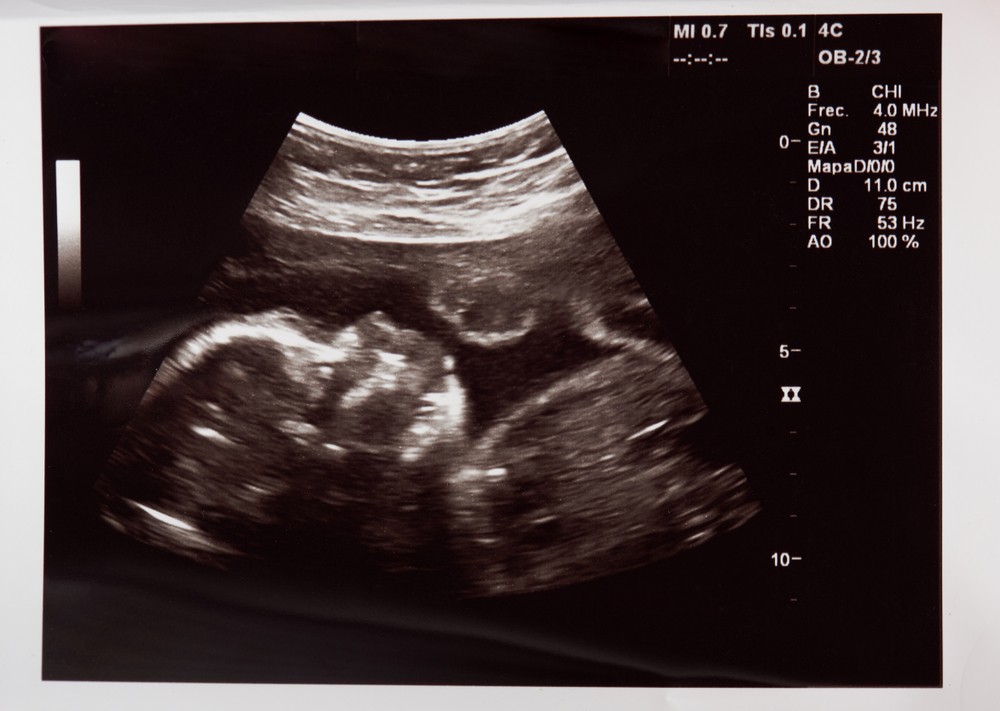

爸爸心痛描述當時知道「豬小弟」離開佢哋,內心完全無法接受:「七個月喇,再兩個月你就要出生,亦都係農曆一月一日,大家高高興興要迎接你嘅到來⋯⋯爸比跟媽咪今天例行產檢嘅時候聽到醫生話你無心跳,爸比我當下以為你喺到同我講笑嗎?」

所有事都嚟得太突然,爸爸指囝囝離開前,老婆身體完全無異樣,亦無出血,一啲先兆都無,醫生突然話囝囝已經無心跳,依嗰消息令佢哋兩老婆瞬間崩潰,完全無法接受。